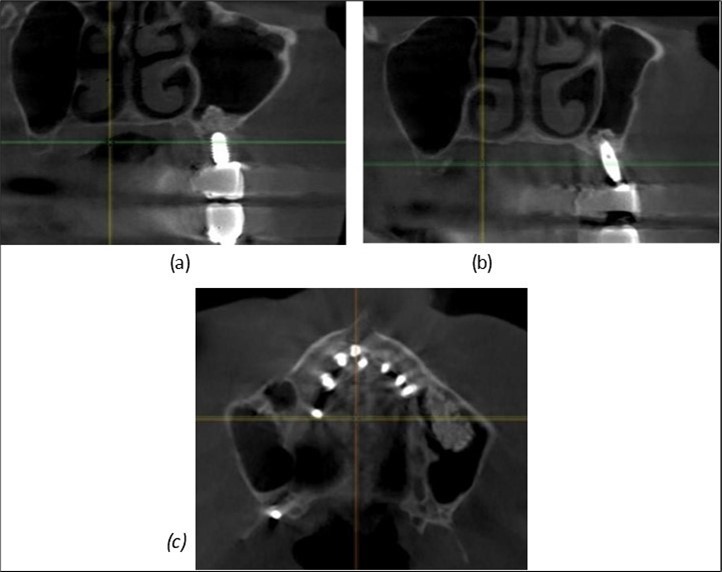

Figure 8.(a), (b) Sinus lift and grafting area with two stage implants before their removal. (c) area of fixation of BCS and TPG implants, avoiding the sinus lift and grafting area

Figure 9.Implants in the pterygoid plateau area: (a) TPG implant fixed in the maxillary-sphenoid junction area, quadrant 1; (b) TPG implant fixed in the maxillary-sphenoid junction area, quadrant 2.

Figure 10.Implants in the palatal sinus cortical area to avoid bone grafting: (a) BCS implant partially fixed in the graft material mass, partially in the palatal cortex; (b) Implant fixed in the palatal cortex at the junction with the nasal cortex, behind the graft material mass.